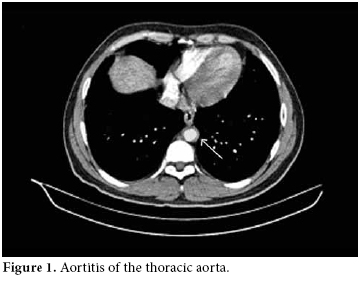

A 28-year-old male patient was admitted to our hospital with complaints of severe abdominal pain and nausea which had started six weeks previously. There were painful, maculopapular lesions that responded well to a topical steroid in both of the palms. The patient had also been suffering from photosensitivity for the last eight months. He had been diagnosed with type 1 diabetes mellitus (DM) and prothrombin 20210a gene mutation during the last 12 years and he had also a history of deep vein thrombosis (DVT) in 2002 and pulmonary thrombo embolism (PTE) in 2006. His mother also had a history of prothrombin 20210a gene mutation and type I DM. He was being treated with a daily dose of glargine insulin and warfarin. His physical examination at the time of admission revealed hypertension (170/100 mmHg), maculopapular lesions on both palms, hepatosplenomegaly, and abdominal tenderness. The laboratory examination was as follows: white blood cells (WBC) counts 15000/mm3, hemoglobin 16.3 gr/dl, platelets 92 000/mm3, blood urea nitrogen (BUN) 20 mg/dl, creatinine 1.46 mg/dl, erythrocyte sedimentation rate (ESR) 40 mm/h, C-reactive protein (CRP) 8.8 mg/dl (0-0.8), and fibrinogen 712 mg/dl (219-403). A urinalysis presented the following results: +++protein, +++blood, no casts, and microprotein in 24 h urine 900 mg/day (0-80). The serologic tests were the followiong: anti-nuclear antibodies 1/320 (homogeneous pattern), anti-double-stranded deoxyribonucleic acid (anti‐dsDNA) 1.7 (0-1.1), rheumatoid factor 22.0 IU/mL (0-15), anti-cardiolipin IgG>300 GPL/mL (0-15), and anti-phospholipid IgG 232 GPL/mL (0-15). A chest X-ray showed minimal pleural effusion and the electrocardiography ECG was normal. There was no thrombus and no vegetation in the transesophageal echocardiography (TEEC). For further evaluation of the thrombocytopenia, bone marrow aspiration and a biopsy were performed, but there were no pathological findings to explain the situation. Also, a skin biopsy from the palms was done to search for the etiology, but this also yielded no clues. Angiography with abdominal computed tomography revealed a thickening of the wall of the thoracic and abdominal aorta and an increased density of the surrounding fat tissues at the level of bifurcation. These were compatible with the diagnosis of vasculitis and retroperitoneal fibrosis (figures 1 and 2).